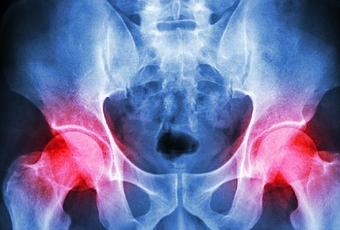

El dolor de cadera es cualquier tipo de dolor o molestia que involucra las caderas. Sin embargo, lo interesante de dolor de cadera es que no siempre se hace sentir en la cadera. A veces, el dolor se siente en la ingle o incluso en el muslo.

El dolor de cadera puede ser causado por una variedad de cosas. Una fractura de cadera puede causar inmensas cantidades de dolor y ser muy debilitante. De hecho, menos el 50% de los pacientes que sufren de dolor en la cadera, es debido a una fractura de retorno a su anterior nivel de actividad. Se necesita una cirugía para reparar una fractura de cadera y las complicaciones son altamente posibles. Otra causa de dolor en la cadera es un flujo sanguíneo insuficiente a la cadera, como la necrosis aséptica, una afección ósea, que ocurre como resultado de la falta de riego sanguíneo en el hueso de la cadera, puede causar dolor, incluso la muerte. La artritis, la osteoporosis, la bursitis, tendinitis y todos pueden causar dolor de cadera, también.